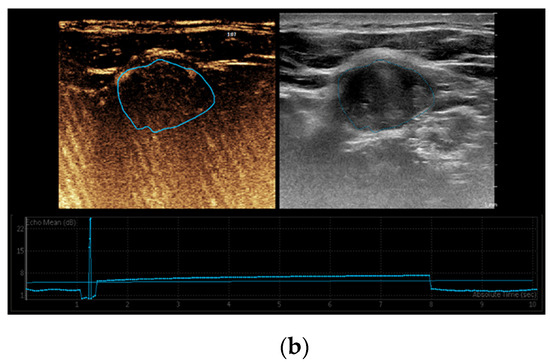

Despite significant achievements in surgical techniques for DTC throughout recent decades, ranging from conventional open thyroidectomy to endoscopic thyroidectomy, postoperative complications such as permanent recurrent laryngeal nerve palsy, hypoparathyroidism, and infection continue to be reported in contemporary research. Over the last years, active surveillance (AS) has been proposed as a viable alternative for surgical excision in patients with PTC with diameter ≤ 10 mm, defined as intrathyroidal papillary microcarcinomas (PTMC), particularly individuals who are at high surgical risk and/or anticipated limited longevity (Figure 2). Regardless of the encouraging results of AS, implementation in clinical practice is significantly impacted by psychosocial factors, patient comorbidities, and motivation [21,74]. Therefore, some patients prefer to tolerate relatively aggressive interventions as an alternative to AS.

Figure 2.

A 52 years old male with multifocal papillary thyroid carcinoma developed on multinodular goiter. (a) Quantitative shear wave elastography (SWE) revealed 38.8 kPa; (b) qualitative contrast-enhanced ultrasound (CEUS) of the nodule revealed heterogenous hypo-enhancement and quantitative CEUS revealed a time to peak of 10.07 s and a peak intensity of 3.18 dB.